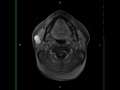

Benign Mixed Tumor, Parotid (Pleomorphic Adenoma)

54-year-old male with right-sided facial swelling. There is a circumscribed, T1-hypointense, T2/STIR-hyperintense, enhancing reniform shaped mass arising in the superficial right parotid gland which restricts diffusion. The differential includes benign mixed parotid tumor (pleomorphic adenoma), parotid cystic carcinoma, mucoepidermoid carcinoma, Warthins tumor, metastatic nodes and non-Hodgkin lymphoma. This was a case of benign mixed parotid tumor. Worrisome clinical features concerning for malignant transformation include facile nerve paralysis, multifocal involvement, and rapid enlargement. Worrisome imaging features include: infiltrative margins, multicentricity, or regions hypointense T2 signal. Females are affected 2x as often as males. Treatment is with complete surgical resection including the tumor capsule and adequate margins.